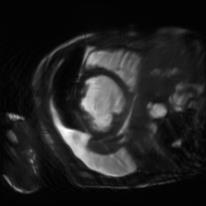

Recently, deep neural networks have greatly advanced undersampled Magnetic Resonance Image (MRI) reconstruction, wherein most studies follow the one-anatomy-one-network fashion, i.e., each expert network is trained and evaluated for a specific anatomy. Apart from inefficiency in training multiple independent models, such convention ignores the shared de-aliasing knowledge across various anatomies which can benefit each other. To explore the shared knowledge, one naive way is to combine all the data from various anatomies to train an all-round network. Unfortunately, despite the existence of the shared de-aliasing knowledge, we reveal that the exclusive knowledge across different anatomies can deteriorate specific reconstruction targets, yielding overall performance degradation. Observing this, in this study, we present a novel deep MRI reconstruction framework with both anatomy-shared and anatomy-specific parameterized learners, aiming to "seek common ground while reserving differences" across different anatomies.Particularly, the primary anatomy-shared learners are exposed to different anatomies to model flourishing shared knowledge, while the efficient anatomy-specific learners are trained with their target anatomy for exclusive knowledge. Four different implementations of anatomy-specific learners are presented and explored on the top of our framework in two MRI reconstruction networks. Comprehensive experiments on brain, knee and cardiac MRI datasets demonstrate that three of these learners are able to enhance reconstruction performance via multiple anatomy collaborative learning.